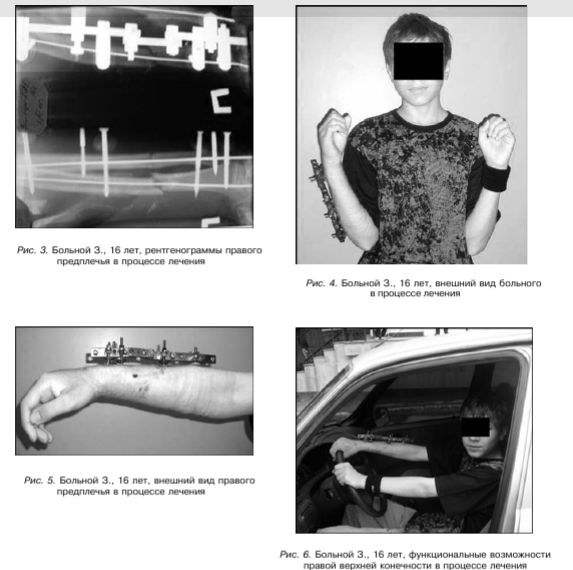

После обработки операционного поля введены консольные стержневые фиксаторы путем ручного вкручивания в метафизарные и диафизарные отделы костей предплечья. Стержни закреплены с помощью кронштейнов во внешних опорах (рис. 3 - 7).

Аппараты демонтированы через 3,5 месяца. Ось предплечья правильная. Движения в локтевом и лучезапястном суставах в полном объеме (рис. 8).